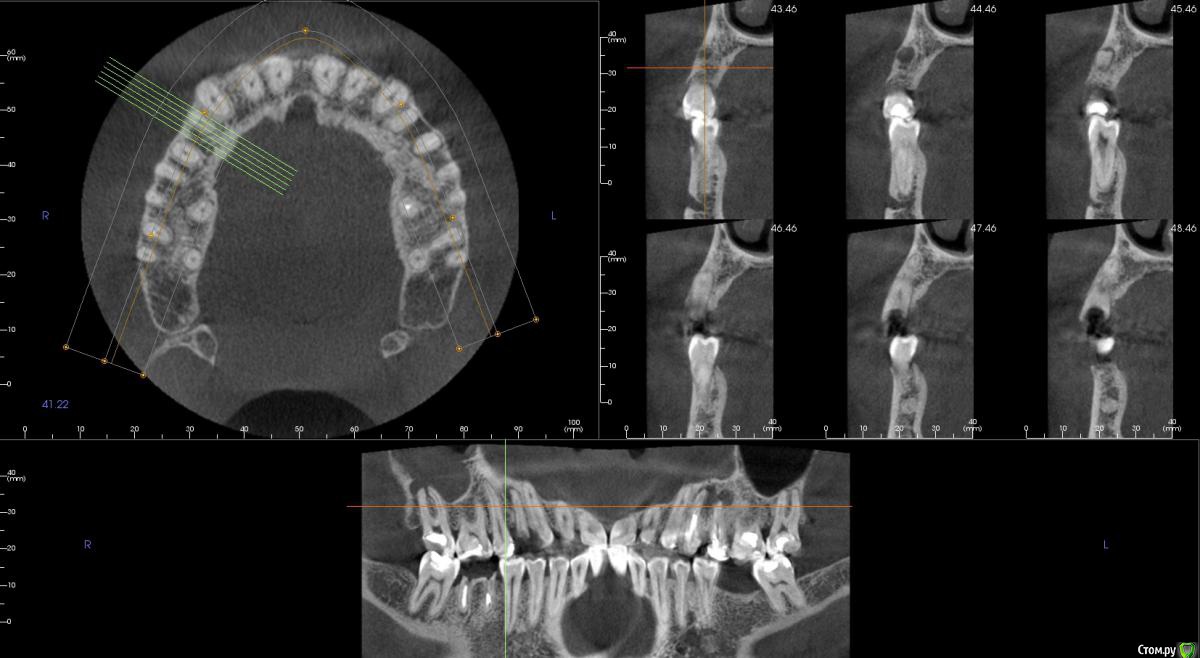

kamranchick Опубликовано 5 ноября, 2015 Поделиться Опубликовано 5 ноября, 2015 Добрый день уважаемые форумчане)Хочу посоветоваться с Вами.Пациент обратился по поводу 14 зуба, хочет удалить и поставить имплантатаБыло предложено идти но одномоментную имплантацию.Вопрос - есть ли противопоказание в данном случае? нужно ли аугментация?Я рассматриваю варианты с устновкой имплантата ALpha Bio SPI 3.3 -13мм, и установка формика с шашлычком(так как бугры хорошие), при условии хорошего торкаВаши советы... Ссылка на комментарий

bullbull Опубликовано 6 ноября, 2015 Поделиться Опубликовано 6 ноября, 2015 Диаметр можно и побольше, как мне кажется. Ссылка на комментарий

kamranchick Опубликовано 6 ноября, 2015 Автор Поделиться Опубликовано 6 ноября, 2015 А удастся ли поставить osstem 3.5 на 11.5, подойдёт ли он для одномоментный? Спрашиваю с целью того, что есть в наличии этот имплантат Ссылка на комментарий

gum Опубликовано 6 ноября, 2015 Поделиться Опубликовано 6 ноября, 2015 Коллега диаметр однозначно больше 3,5 или 3,75, а то что нет в наличии, так закажите. Можно и формик без проблем. Ссылка на комментарий

faity Опубликовано 10 ноября, 2015 Поделиться Опубликовано 10 ноября, 2015 По сути переапикальные изменения обусловленны инфекцией непосредственно в каналах и после удаления причинного зуба, даже при наличии остаточной МО в костной ткани это никак не мешает приживлению импланта.Но к сожалению мои выводы основанны исключительно на литературных данных в этой области, т.к. я не дядя Карен и не имею возможности проводит гистологические исследования По топику: апекс импланта я бы немного вестибулярнее расположил, чтобы шахта выходила на бугры, а не на вестибулярную стенку и по длине такой, чтобы якорнулся в кости хотя бы на 1 мм Ссылка на комментарий

kamranchick Опубликовано 10 ноября, 2015 Автор Поделиться Опубликовано 10 ноября, 2015 По сути переапикальные изменения обусловленны инфекцией непосредственно в каналах и после удаления причинного зуба, даже при наличии остаточной МО в костной ткани это никак не мешает приживлению импланта.Но к сожалению мои выводы основанны исключительно на литературных данных в этой области, т.к. я не дядя Карен и не имею возможности проводит гистологические исследования По топику: апекс импланта я бы немного вестибулярнее расположил, чтобы шахта выходила на бугры, а не на вестибулярную стенку и по длине такой, чтобы якорнулся в кости хотя бы на 1 ммПридется выбирать. либо идти по небной стенке, либо в правильной ортопедической позиции, а можно ли сразу 2 зайца убить в данном случае? боюсь при удалении дефект будет большим. Ссылка на комментарий